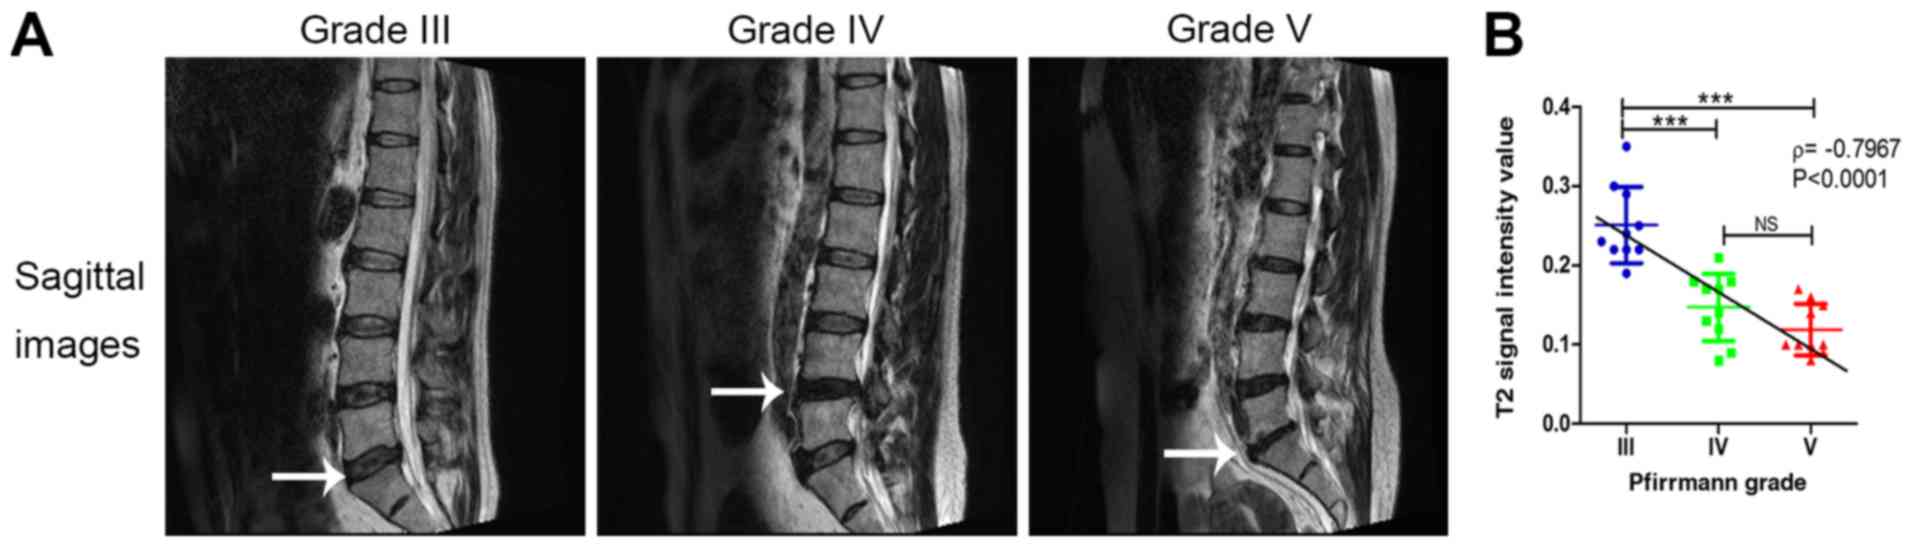

Representative MRI images of different patients are provided in Fig. 1A. The κ value of the first measurement was 0.734, indicating a good interobserver agreement (P<0.001) and the κ value of the second measurement was 0.774 (P<0.001). The grading results are listed in Table I: Grade III, n=10; grade IV, n=10; and grade V, n=10. None of the discs were graded as Pfirrmann grade I or II.

Figure 1

(A) Representative MRI scans of IDD in different Pfirrmann grades. Sagittal T2-weighted images of lumbar spines with different Pfirrmann grades. The white arrows indicate the location of impaired intervertebral discs. (B) Comparison of the T2 signal intensity value in different Pfirrmann grades. Spearman's rank correlation analysis demonstrated that the T2 signal intensity value was significantly inversely correlated with the Pfirrmann grade. ***P<0.001. NS, no significance; IDD, intervertebral disc degeneration.

The T2 signal intensity value in patients with Pfirrmann grade IV and V was significantly lower compared with that in grade III (P<0.001); however, the T2 signal intensity value was not significantly different between grade IV and grade V (P>0.05). Spearman's rank correlation analysis demonstrated that the T2 signal intensity value was significantly inversely correlated with the Pfirrmann grade (r=-0.7967, P<0.0001; Fig. 1B).